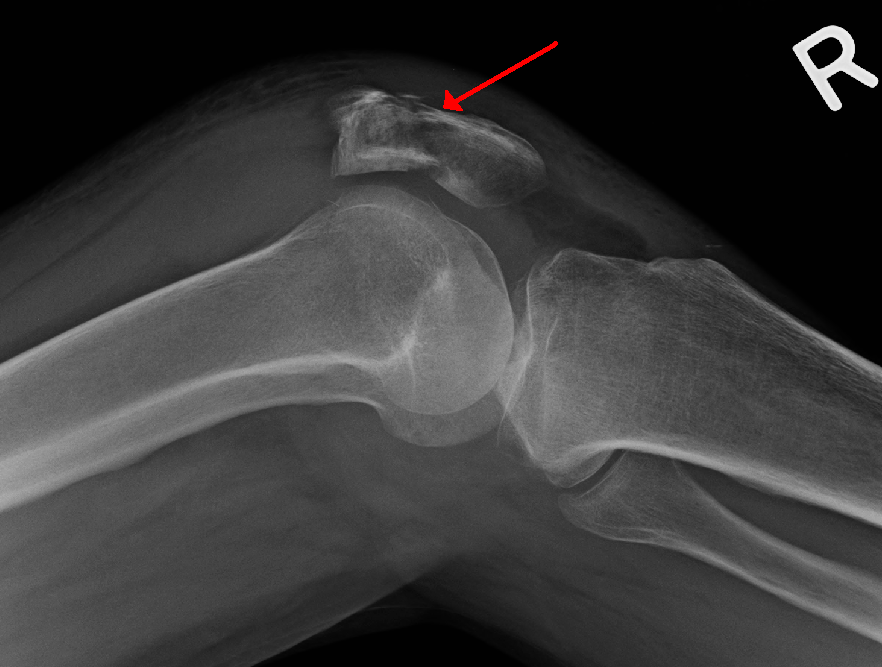

Fracture of Patella

Classifications of fracture of patella:

A) Undisplaced :

1) Transverse fracture these account for nearly 50-80 percent of cases. About 80 percent occur in the middle-third.

2) Stellate fracture.

3) Vertical fracture.

B) Displaced: If displacement is >3 mm and if articular incongruity > 2 mm.

1) Transverse involving upper or lower poles (50-85%).

2) Oblique fracture.

3) Vertical fracture (12-27%).

4) Comminuted fracture (30-35%). 5) Polar-could be proximal or distal.

6) Osteochondral fractures.

Clinical features of fracture of patella:

1. Hi story of trauma.

2. Pain & swelling at the knee joint.

3. The patient is unable to extend the knee.

4. Both the active & passive movements are restricted.

5. On examination :

a) There could be a palpable gap.

b) Tenderness.

c) Signs of effusion.

d) A positive patellar tap.